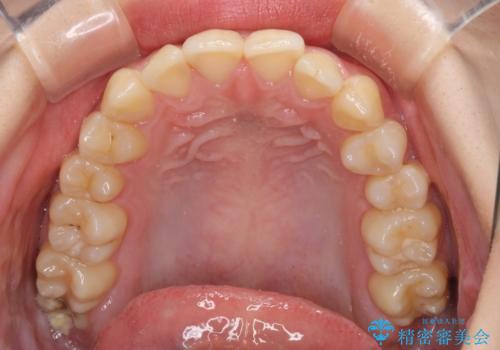

- 上下前歯のデコボコを気にして来院された患者様です。

以前矯正をした後戻りということで、歯列不正はそれほど大きくなかったため、インビザライン・ライトを用いて矯正治療を行うこととしました。

前歯のデコボコが残っており、シミュレーション通りに動いていない部分がありましたが、再矯正であることやご本人の満足いくところまでデコボコが改善されたとのことで、治療を終了することとしました。